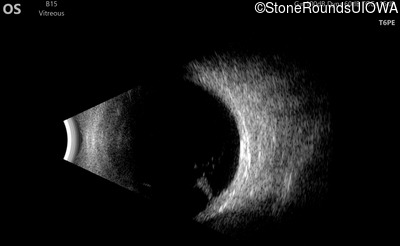

Visit at age: 12 years (Visit 2)

B-Scan Ultrasonography - Left - 20/300

Exemplar